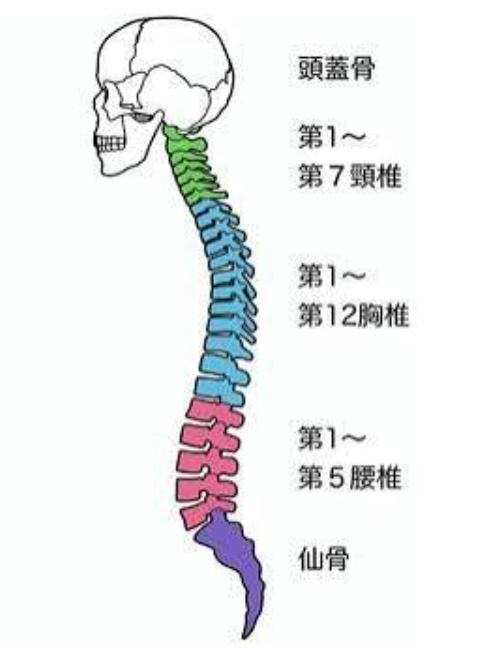

腰椎は5つの骨構成されています。

腰の骨は、

上から下へ L1〜L5 の5つがあります。

それぞれの骨の間には、

椎間板というクッションが挟まっており、

体重や衝撃を吸収しています。

腰椎椎間板ヘルニアが起こりやすいのは、

① L4/L5(第4腰椎と第5腰椎の間)

② L5/S1(第5腰椎と仙骨の間)

です。

この2か所で、全体の約8〜9割を占めると言われています。